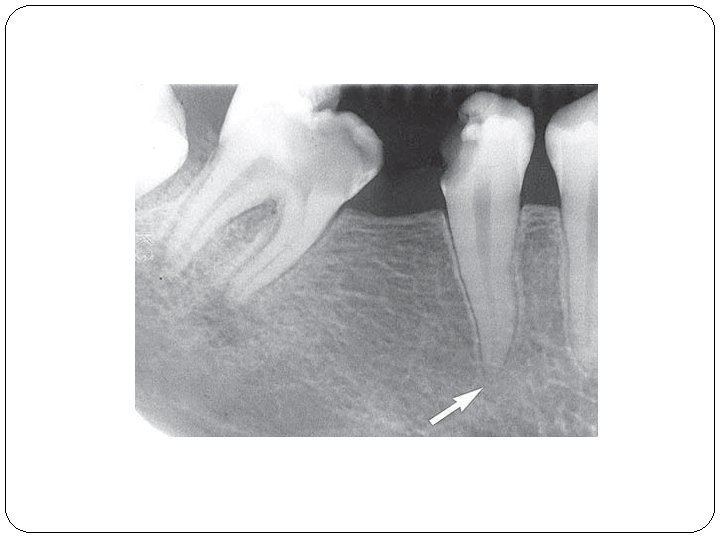

II/B Parodontitis periapicalis chronica �Chronische Wurzelhautentzündung �Symptome: Es gibt sehr oft keine Symptome. �Röntgen: Periapikale Aufhellung-(Grenze ist nicht so scharf) Parodontalspaltverbreiterung �Histologie: Cyst > 1 cm (Fluidum) Granuloma < 1 cm (Granulationsgewebe)

Eine Variation: Parodontitis lateralis chronica �Es gibt Seitekanale nach mesiale oder nach distale Richtung. Die Veränderung erscheint neben der Wurzel. �Symptome: Keine Schmerzen, Devitalität des betroffenen Zahnes. �Röntgen: rundliche Aufhellung im lateralen Parodontium.